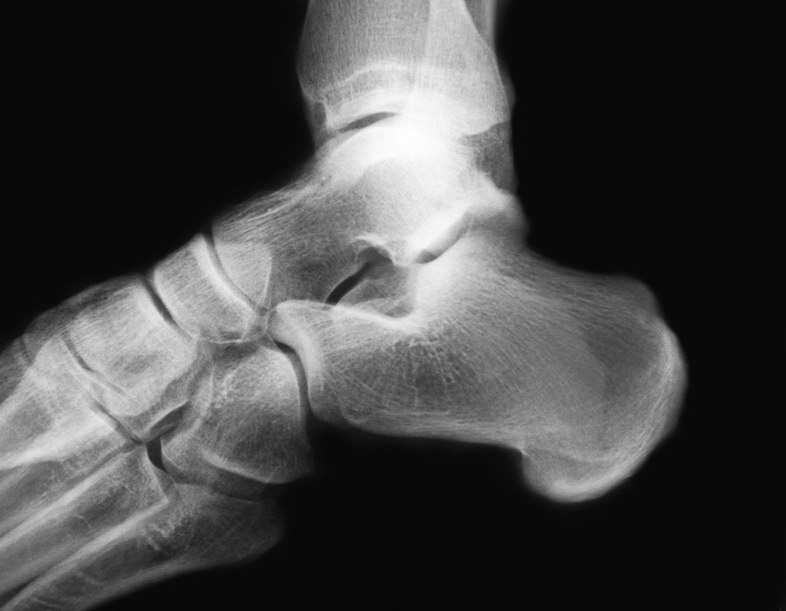

Rx Fractura En Talon . Web las fracturas calcáneas producen diferentes señales y síntomas, dependiendo de si son fracturas traumáticas o por sobrecarga. Web cuando el calcáneo está fracturado, el talón está dolorido y, por lo general, el pie y el tobillo están hinchados y no soportan el.

Ángulos de gissane (blanco) y böhler (negro). Web los síntomas de una fractura de talón incluyen dolor, hinchazón y moretones en el talón. Web las fracturas del calcáneo (hueso del talón) se suelen producir como resultado de una gran fuerza.

Ángulos de gissane (blanco) y böhler (negro). Presenta tres carillas articulares (1, 2, 3) para el. Web las fracturas del calcáneo (hueso del talón) se suelen producir como resultado de una gran fuerza. El calcáneo es el hueso que más frecuentemente se fractura del tarso, el 75% de las fracturas son intraarticulares y su tratamiento sigue siendo hoy en día objeto de debate.

Rx Fractura En Talon - Ángulos de gissane (blanco) y böhler (negro). Web cuando el calcáneo está fracturado, el talón está dolorido y, por lo general, el pie y el tobillo están hinchados y no soportan el. El diagnóstico se realiza mediante radiografía y, de. Web las fracturas del calcáneo (hueso del talón) se suelen producir como resultado de una gran fuerza. Web los síntomas.